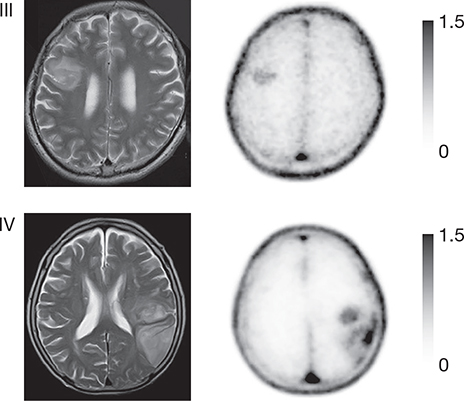

Fig 6

Figure 6. T1-weighted post-contrast (cT1), T2-weighted (T2), 18F-FLT PET ([18]F-FLT) and 18F-FET ([18]F-FET) images of a patient with a non-enhancing glioblastoma, WHO grade IV. The lesion is hyperintense on the T2-weighted image but does not show contrast enhancement. Increased uptake in the T2-hyperintense region can clearly be seen on the 18F-FET PET image, but there is no uptake visible on the 18F-FLT PET image, illustrating the drawback of PET agents that cannot easily cross the BBB. This figure is reproduced – with new figure legend appropriate for current article – from Nowosielski et al. (2014), Figure 1, under the terms of the Creative Commons Attribution 4.0 International (CC BY) License (http://creativecommons.org/licenses/by/4.0) (107).